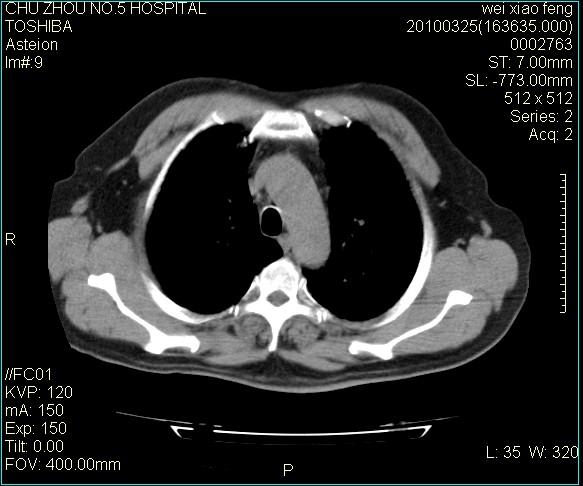

男,60岁,反复咳、痰、喘3月,加重3天。

双肺间质性改变。

双肺间质纤维化,双肺血型潘散肺结核。

考虑尘肺

间质病变,间质炎症,间质纤维化趋势